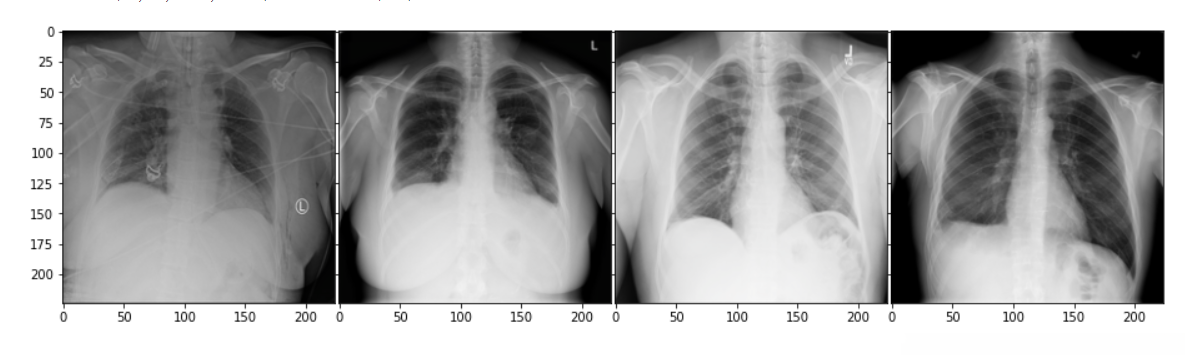

数据集样子